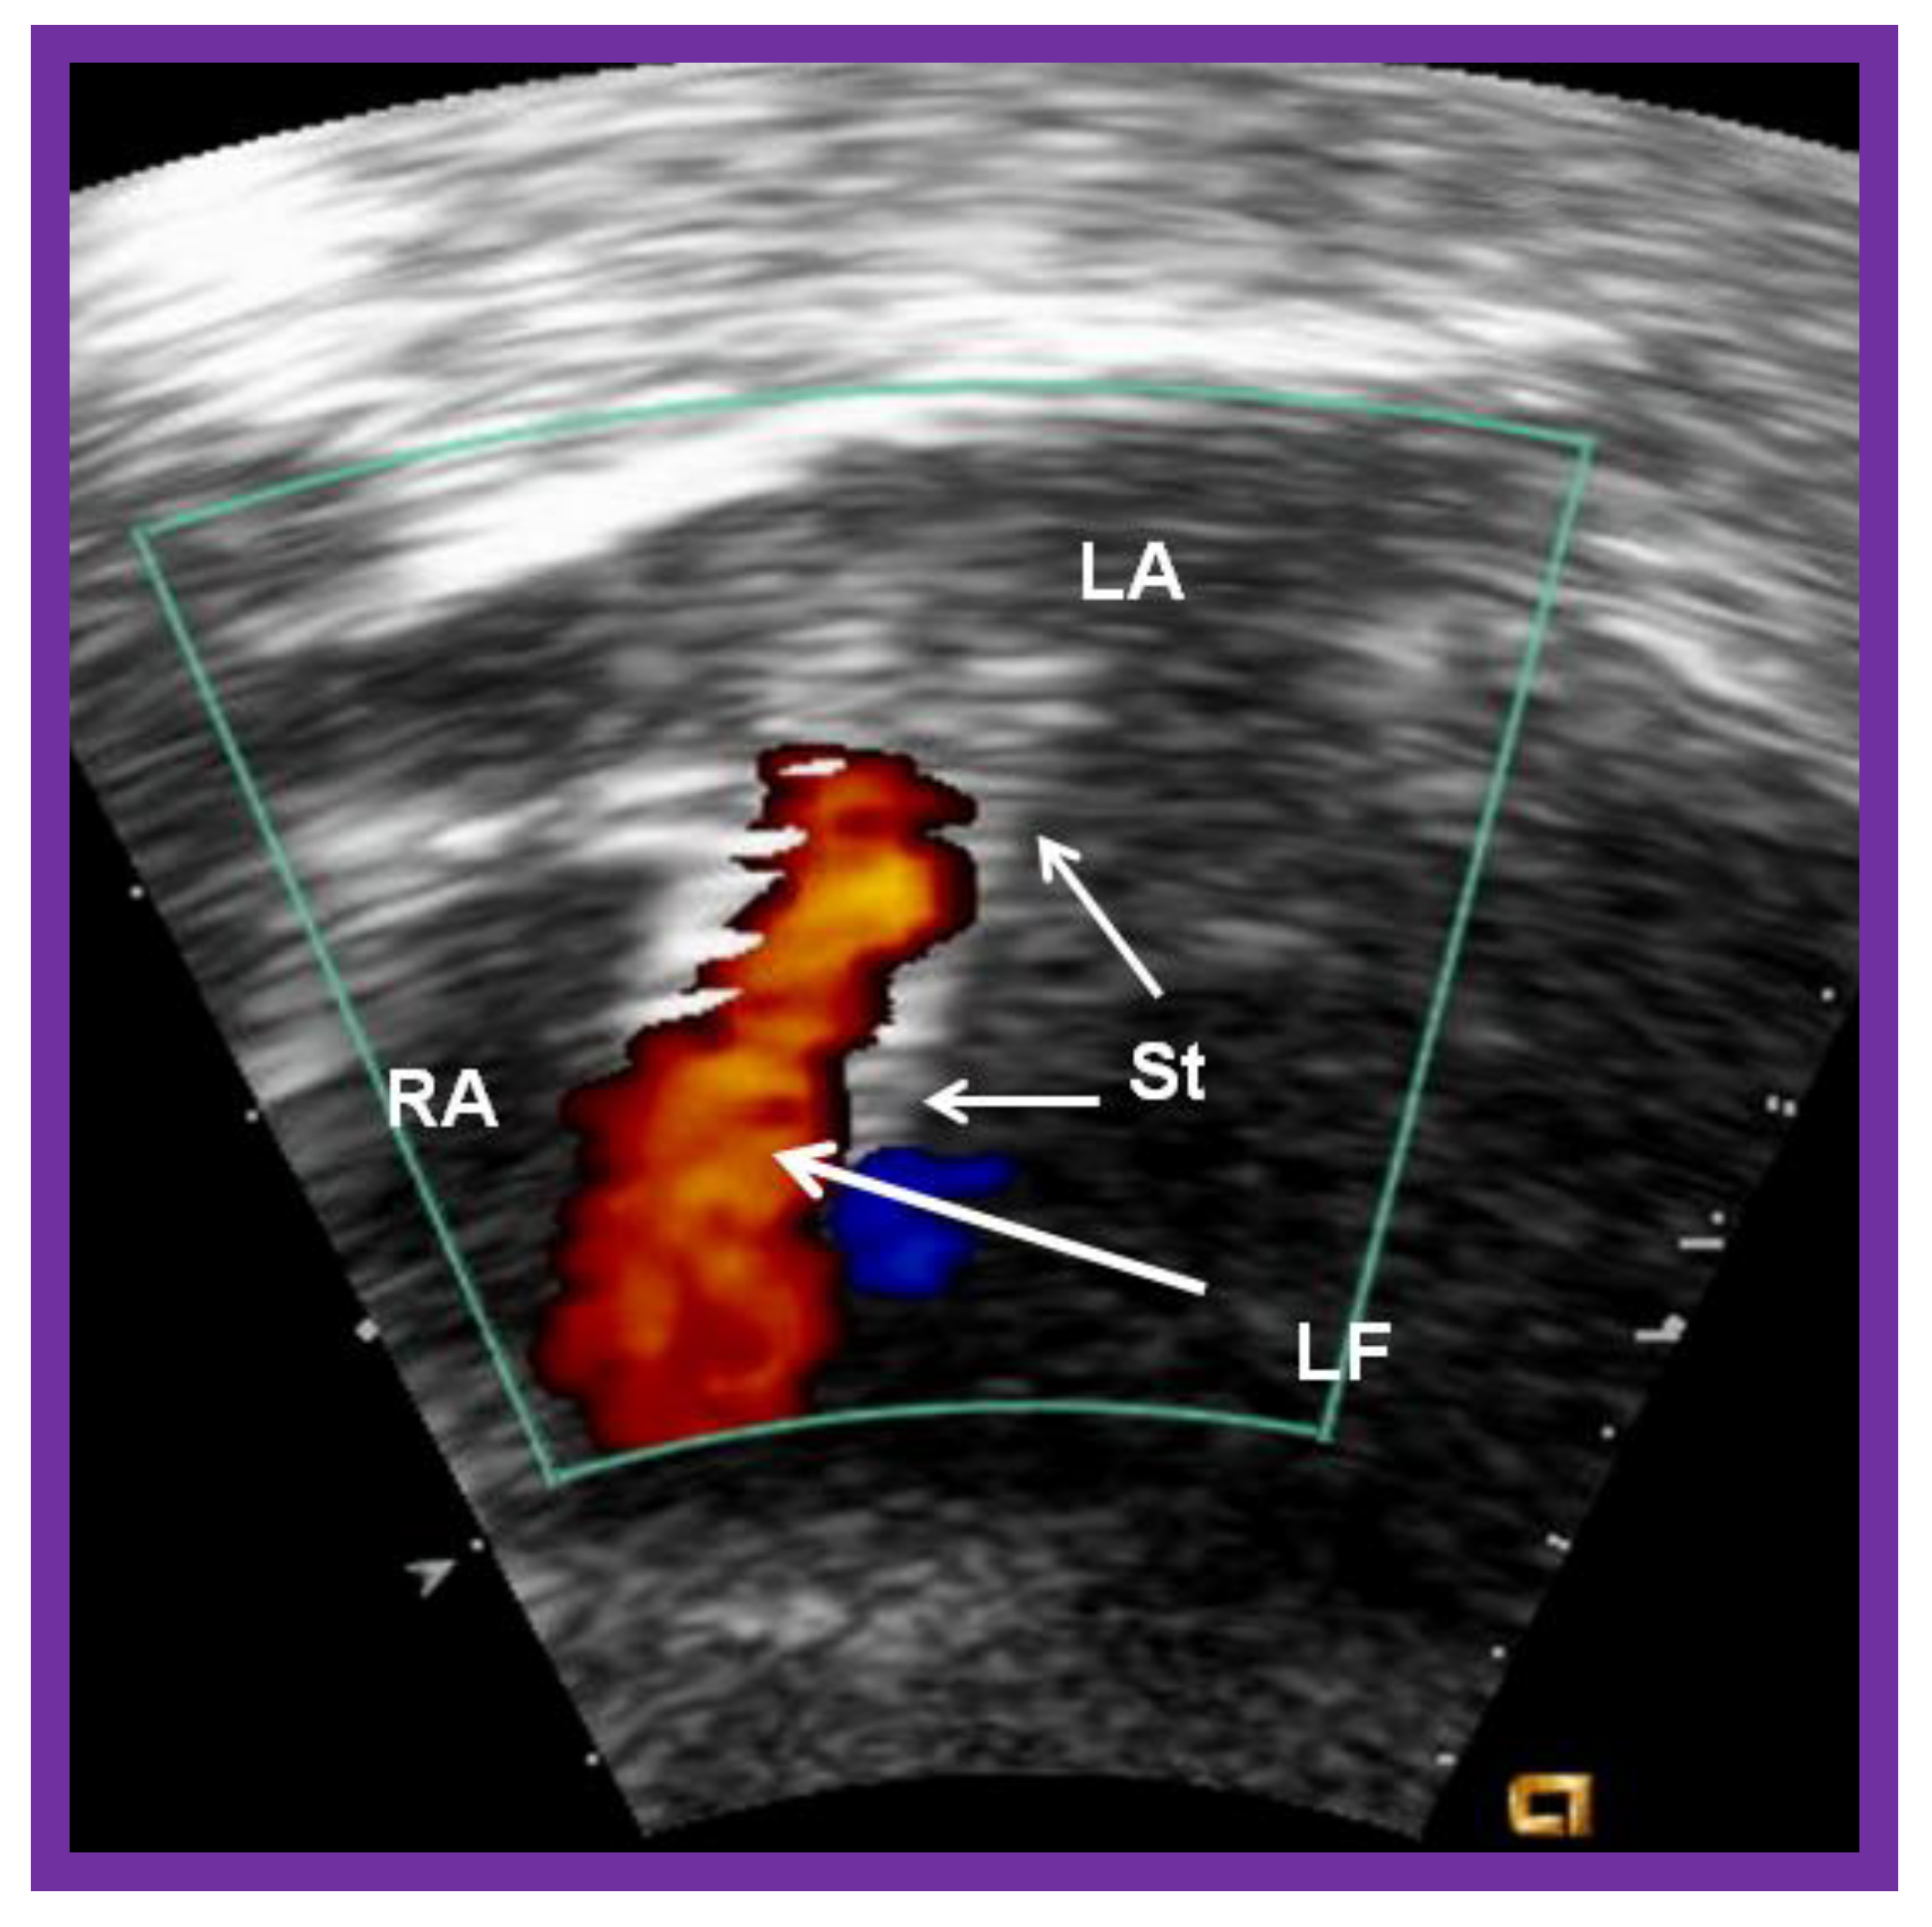

5.1. Restrictive Atrial Communication

Obstruction of PFO/ASD may manifest either as systemic venous or pulmonary venous congestion, depending upon the lesion. The obstruction may be confirmed by a small-sized PFO by 2-dimentional echo and high velocity flow across it by Doppler. Once it is detected, it should be promptly relieved. In the majority of babies, Rashkind balloon atrial septostomy [52,58,61] (Figure 12) is successful in relieving the interatrial obstruction. Rashkind septostomy may not be feasible in some patients either because of thick atrial septal tissue and/or small left atria. In such situations, atrial septal restriction may be relieved by static balloon dilatation [54,55] (Figure 18) or stent implantation [55,56,57,58,61,89] (Figure 19 and Figure 20). If transcatheter methods are not feasible or not successful, surgical septostomy becomes necessary.

Figure 20.

Video frame of the stent (St) (short arrows) demonstrates laminar flow (LF) (long arrow) across it. LA, left atrium; RA, right atrium. Reproduced from Reference [89].